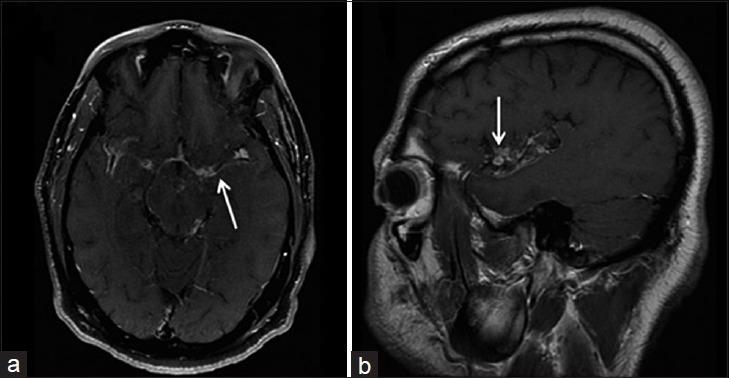

中枢神经系统真菌感染:图文综述

Fungal Infections of the Central Nervous System: A Pictorial Review.

Fungal infections of the central nervous system (CNS) pose a threat to especially immunocompromised patients and their development is primarily determined by the immune status of the host. With an increasing number of organ transplants, chemotherapy, and human immunodeficiency virus infections, the number of immunocompromised patients as susceptible hosts is growing and fungal infections of the CNS are more frequently encountered. They may result in meningitis, cerebritis, abscess formation, cryptococcoma, and meningeal vasculitis with rapid disease progression and often overlapping symptoms. Although radiological characteristics are often nonspecific, unique imaging patterns can be identified through computer tomography as a first imaging modality and further refined by magnetic resonance imaging. A rapid diagnosis and the institution of the appropriate therapy are crucial in helping prevent an often fatal outcome.

中枢神经系统(CNS)真菌感染对免疫功能低下的患者构成威胁,其发病主要取决于宿主的免疫状态。随着器官移植、化疗及人类免疫缺陷病毒感染病例的增多,作为易感宿主的免疫功能低下患者数量不断增加,中枢神经系统真菌感染也更为常见。它们可能导致脑膜炎、脑炎、脓肿形成、隐球菌瘤及脑膜血管炎,疾病进展迅速且症状常相互重叠。尽管影像学特征通常不具有特异性,但计算机断层扫描作为首选成像方式可识别出独特的影像模式,磁共振成像则可进一步完善。快速诊断并采取恰当治疗对于预防往往致命的后果至关重要。